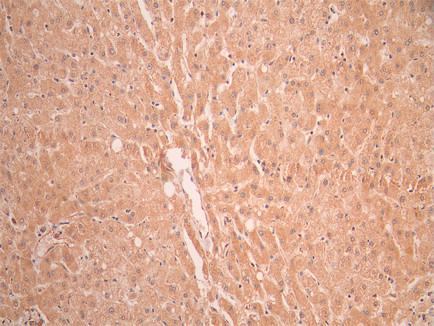

• IHC image of CSB-RA967831A0HU diluted at 1:100 and staining in paraffin-embedded human liver tissue performed on a Leica BondTM system. After dewaxing and hydration, antigen retrieval was mediated by high pressure in a citrate buffer (pH 6.0). Section was blocked with 10% normal goat serum 30min at RT. Then primary antibody (1% BSA) was incubated at 4°C overnight. The primary is detected by a Goat anti-rabbit polymer IgG labeled by HRP and visualized using 0.05% DAB.